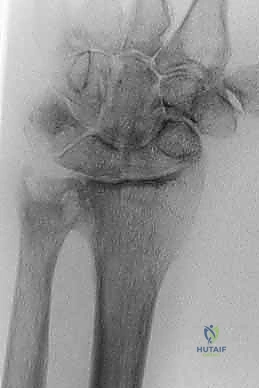

### FIG 2 • A,B. Anteroposterior (AP) and lateral radiographs of extraarticular dorsally angulated malunion. C,D. PA and lateral radiographs of an extra-articular dorsally displaced malunion. E. CT shows rotational deformity associated with a volarly displaced extra-articular fracture. (Copyright Diego Fernandez, MD, PhD.) Lack of motion should be clearly due to malalignment and not due to pain or protectiveness—likewise for instability of the DRUJ. Range of motion: A goniometer is used to measure wrist flexion, extension, radial and ulnar deviation, supination, and pronation. Ulnocarpal compression: The carpus is forcefully ulnarly deviated toward the ulna. Consistent reproduction of usual pain with ulnar deviation tasks is consistent with ulnocarpal impaction. The examiner can test for DRUJ instability by stabilizing the radius and trying to subluxate the distal ulna dorsal and volar from the sigmoid notch of the radius. Substantially, less stability than the opposite side may correlate with symptomatic DRUJ instability, but this is a very difficult and subjective test. Scaphoid shift test: Instability compared to the opposite wrist would indicate a possible scapholunate interosseous ligament tear, indicating a potential dissociative rather than the typical nondissociative carpal malalignment usually associated with distal radius malunion. Grip strength is one of the measure of wrist dysfunction, but it is largely determined by pain and effort—both strongly influenced by psychosocial factors. ## IMAGING AND OTHER DIAGNOSTIC STUDIES PA and lateral radiographs of the wrist ( FIG 2A-D) can be supplemented by specific radiographs for evaluation of the joint surface, particularly for potential articular malunions. Comparison with the opposite, uninjured wrist is useful and serves as a template for surgical correction. CT, particularly three-dimensional CT, is useful to precisely evaluate the joint surfaces ( FIG 2E). Neurophysiologic tests (nerve conduction velocity and electromyography) are ordered to evaluate any symptoms or signs of carpal tunnel syndrome that may need to be addressed. 144 ## DIFFERENTIAL DIAGNOSIS Stiffness: capsular stiffness and tendon adhesions Numbness: idiopathic carpal tunnel syndrome Pain: another discrete source of pain or even nonspecific pain ## NONOPERATIVE MANAGEMENT Nonoperative management is appropriate for low-demand and infirm individuals. Splints are weaned after 6 weeks of cast immobilization. Patients who struggle to regain motion may benefit from working with an occupational therapist or a certified hand therapist. Normal activities are resumed in 3 or 4 months. The patient may return every 2 or 4 months or so until satisfied with the result. Patience is warranted in many situations, particularly for patients with ulnar-sided wrist pain thought to be due to an extra-articular malunion. This discomfort is the last pain to go away after a distal radius fracture and can last up to a year. ## SURGICAL MANAGEMENT Surgery is appropriate when a radiographic deformity correlates with a specific anatomically correctable problem and the deformity is associated with a substantial risk of dysfunction or arthrosis. The patient must understand the risks and benefits of intervening. The surgeon should be wary of pain as the primary complaint because pain is strongly influenced by psychosocial factors, and pain relief is an achievable goal only when consistent with an objective, correctable anatomic deformity such as discomfort clearly associated with a substantial ulnocarpal impingement. When the issue is restriction of motion and there is less than 20 degrees of dorsal tilt or less than 5 mm of ulnar positive variance, a nonoperative approach may be warranted.